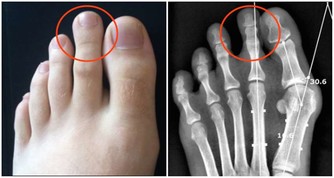

8.胰島細胞勞損,導致糖尿病

晚餐吃得太晚,會因刺激胰島素持續大量分泌,致使分泌胰島素的B 細胞負擔過重,如果是長期的持續超負荷分泌,特別是中老年人則會因B細胞功能衰竭而誘發糖尿病。